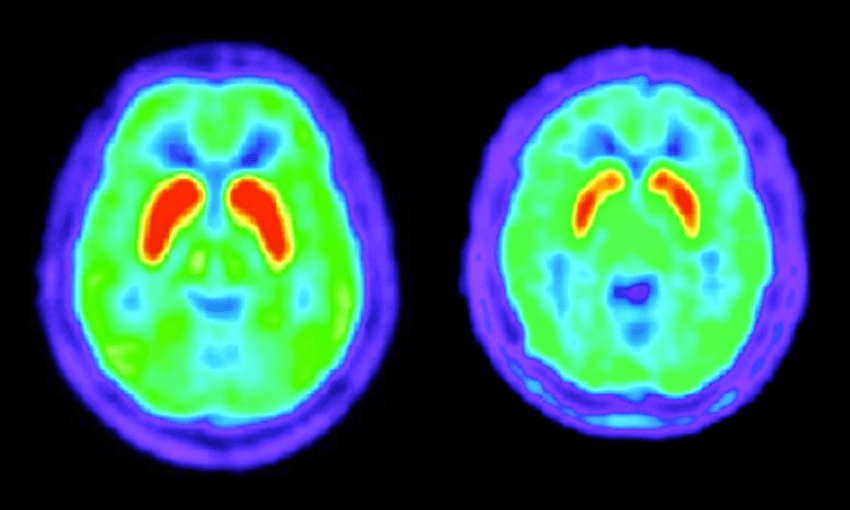

Over the years, researchers began to understand the pathology. In Huntington’s sufferers, the mutated version of the protein Huntingtin is longer. The C-A-G codon in DNA codes for an amino acid, glutamine. This glutamine-rich protein is prone to forming tangles. Eventually, buildup of Huntingtin forms plaques within the brains of sufferers, killing neurons within the motor cortex and causing the symptoms. The more C-A-G repeats within the gene, the longer the glutamine chain within the protein, and the earlier the symptoms begin.